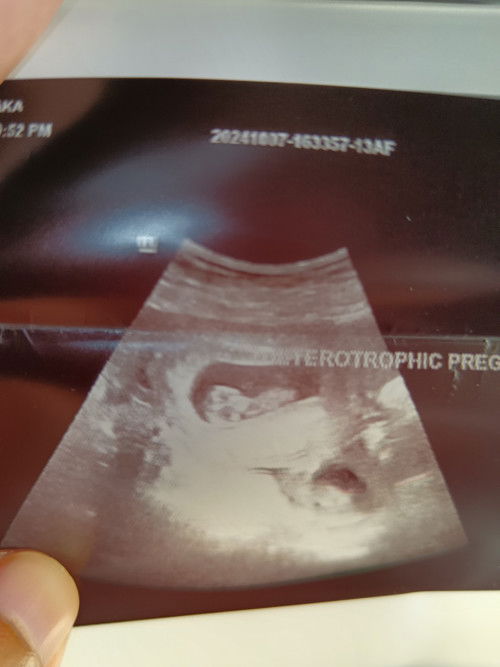

Ectopic Pregnancy..

Ada tak yang senasib dengan saya.. Saya mengandung dalam dan luar rahim.. Dekat dalam rahim ade 1 baby.. Luar rahim ade 1 baby.. Yang di luar rahim sudah operate buang.. Sekarang sy masih hamil 1 lgi baby.. Cuma sy risau baby yg lgi 1 nie berisiko jugak.. Ade tak yg serupa dgan sy yang sedang alami benda yg sama mcm sy?